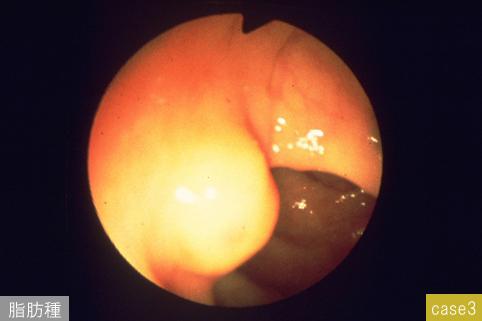

疾患(病理主体)の分類その他/

部位(臓器別)大腸/横行

検査方法内視鏡

病変の最大径(ミリ)10〜14